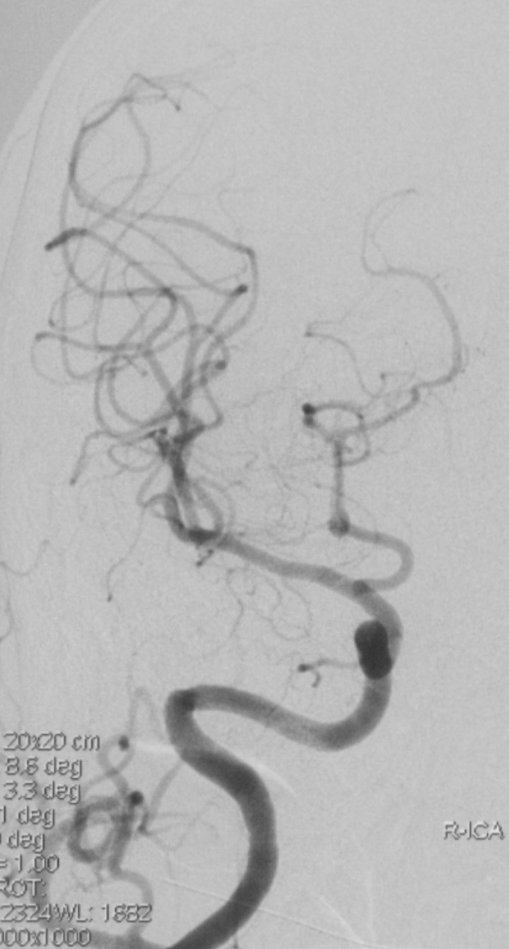

病例二

患者女性,45岁。右侧大脑中动脉M2段闭塞(图7)。采用SNAKE技术裸推6F抽吸导管卡在后交通动脉起始部难以通过。未使用微导丝情况下,导航微导管辅助抽吸导管直接进入大脑中动脉(视频3、视频4)。

为什么要用到微导管介入面对迂曲  创新循迹导航——导航微导管初体验_https://www.jmylbn.com_新闻资讯_第9张

图7